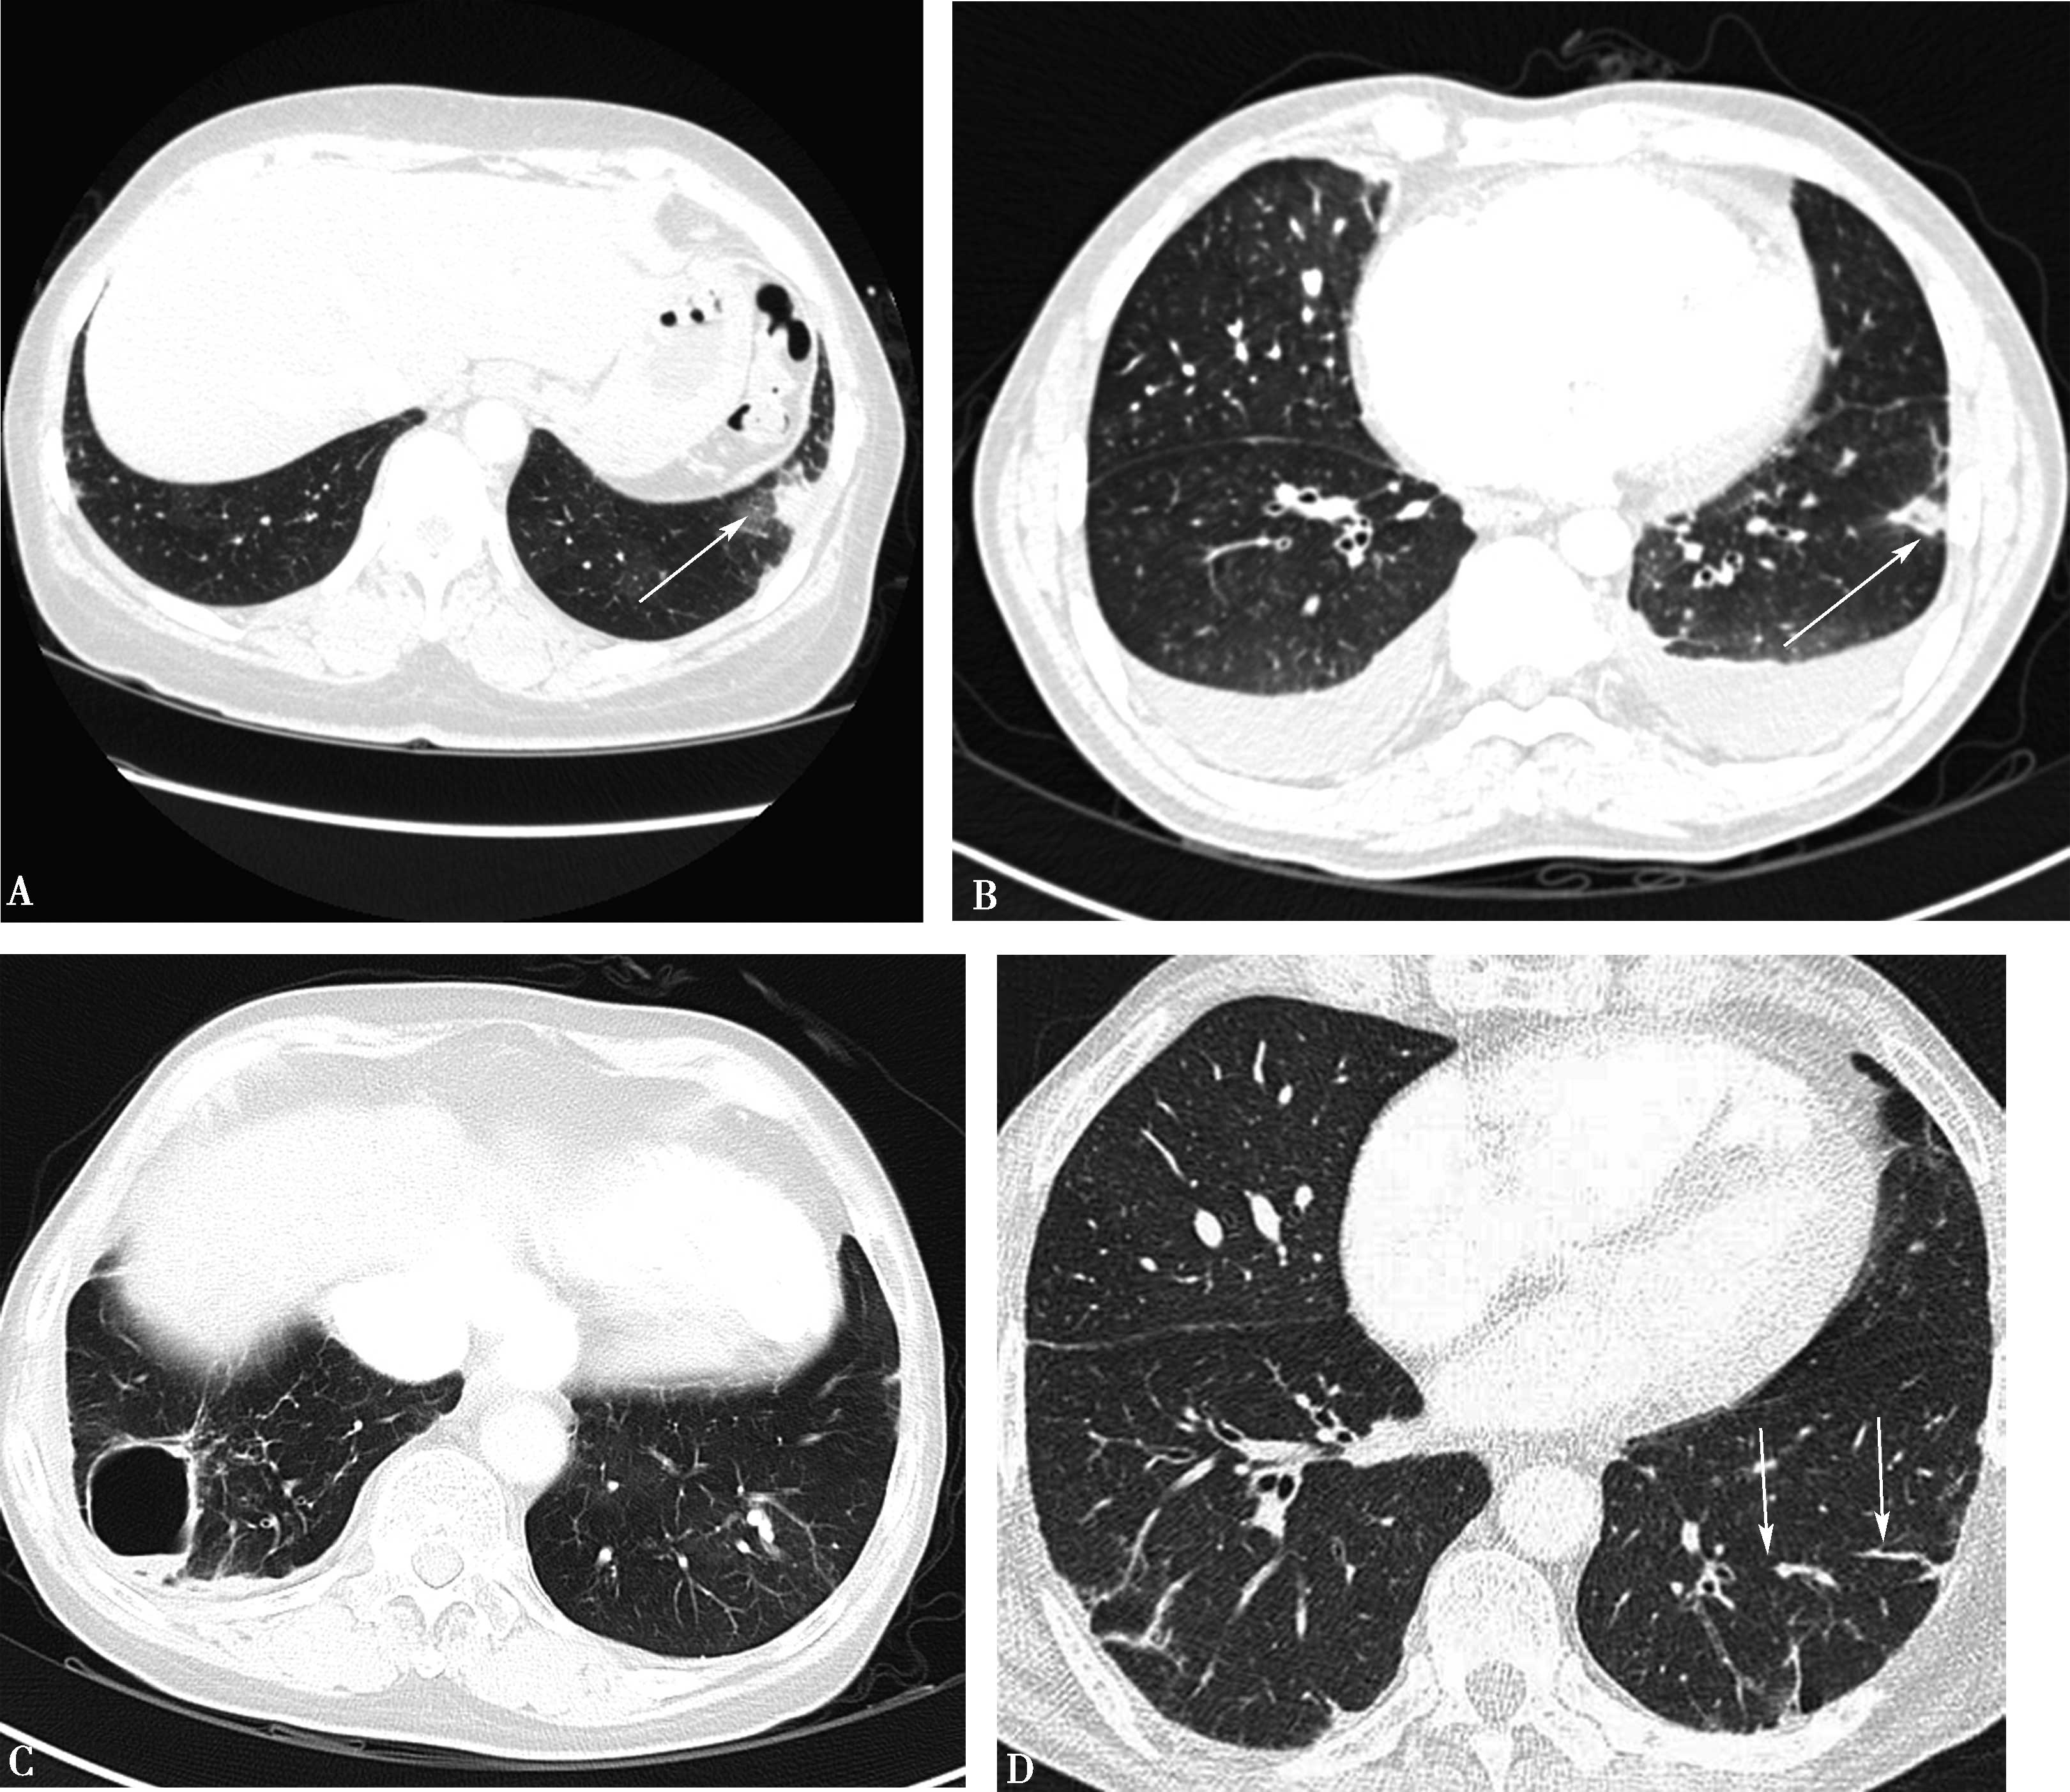

高分辨率CT(平扫)对诊断有重要价值。显示肺实质多发性斑片状、大小不等结节及空洞形成,主要分布两肺中下野,多发性/多样性(不规则,多发,大小不等)为其特点,并存胸膜反应,胸腔积液(图8-5-6)。

图8-5-6 坏死性肉芽肿性血管炎(韦格纳肉芽肿)

A.胸部X线片,两肺多发结节,不规则空洞形成(↑);B~D.横断图像,两上、下肺多发不规则结节肿块,大小不等,不规则空洞形成,壁薄厚不一,边缘不规则,液平形成;病理检查:E.肺小血管横断面,显示炎性细胞浸润累及部分血管;F.肺小血管纵切面,炎性细胞浸润,部分管壁破坏。CT诊断:韦格纳肉芽肿(病理证实为坏死性肉芽肿性血管炎)